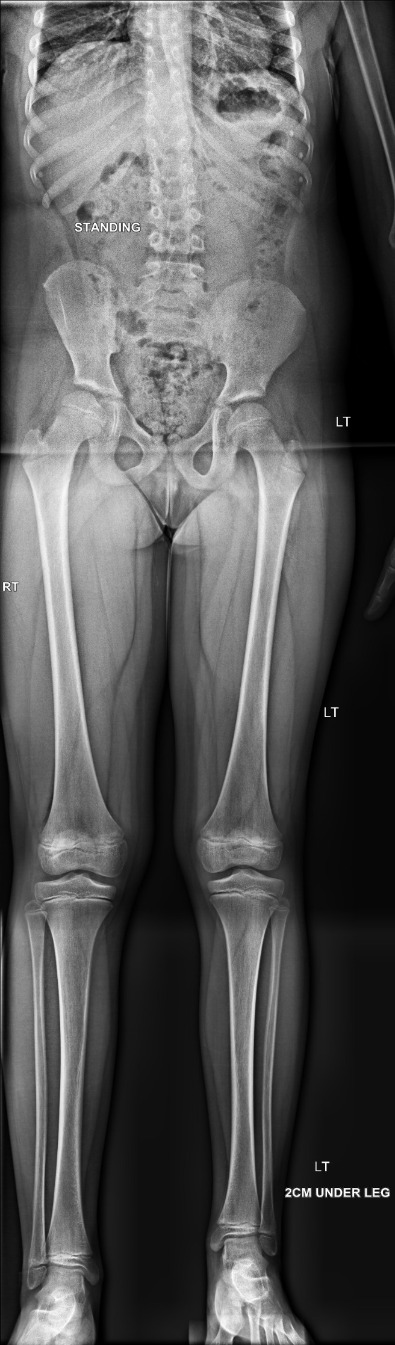

The x-rays below show a case with shortening of the lower limbs (epiphysis).